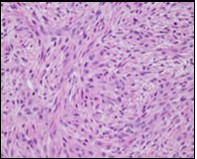

Figure 1.Low grade fibromyxoid sarcoma enunciating fibrous and myxoid zones of uniform spindle-shaped tumour cells with absence of atypia 9.

Macroscopically,the neoplasm is gradually progressive, painless, firm, tan coloured, well circumscribed, grossly infiltrative, soft tissue mass of magnitude varying from one centimetre to 18 centimetres, commonly of 6 centimetres diameter. Cut surface is fibrotic with focal myxoid areas4. On fine needle aspiration cytology, the cellular neoplasm is configured by spindle-shaped cells. Tumour cells contain scant, wispy cytoplasm, uniform, elongated nuclei and miniature, inconspicuous nucleoli. The background is prominently myxoid. Significant nuclear pleomorphism or mitotic activity is absent. However, cogent diagnosis on cytology may be challenging 4.5. On low power, the well demarcated neoplasm is composed of alternating foci of myxoid and fibrous tissue. Giant rosettes are intermingled with zones of whorled cellular aggregates recapitulating preliminary rosettes.

Bland tumour cells depict monotonous, hyperchromatic nuclei. Tumour areas can exhibit prominent curvilinear, arching or plexiform vasculature. Mitotic activity is exceptional 4, 5.

Typically, low grade fibromyxoid sarcoma is comprised of a whorled cellular pattern with intermingled fibrous and myxoid areas. Also, minimally cellular areas of collagenous tissue are denominated, composed of uniform spindle-shaped cells4, 5. Unique morphologic pattern of hyalinising spindle cell tumour configuring giant rosettes can appear in certain low grade fibromyxoid sarcomas4, 5.

The minimally to moderately cellular neoplasm is composed of bland, fusiform or spindle-shaped cells with scarce cytoplasm and angulated nuclei. Also, whorled cellular aggregates are exhibited. Focal to diffuse cellular whorls are intermingled within a dense, collagen-rich stroma. Abrupt, focal transition to myxoid areas can be discerned. Roughly 45% neoplasms depict foci of epithelioid cells. Nearly 40% tumours display enlarged, inadequately configured collagen rosettes2, 4.